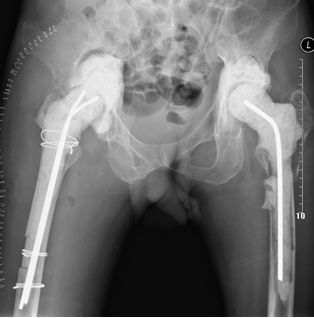

70岁女性,THA术后1年松动,翻修术后仍有疼痛,生活不能自理

第二次翻修取出的臼、柄、骨水泥块,肉芽肿组织

第三次翻修术后3年,髋关节无痛,功能可,生活可以自理